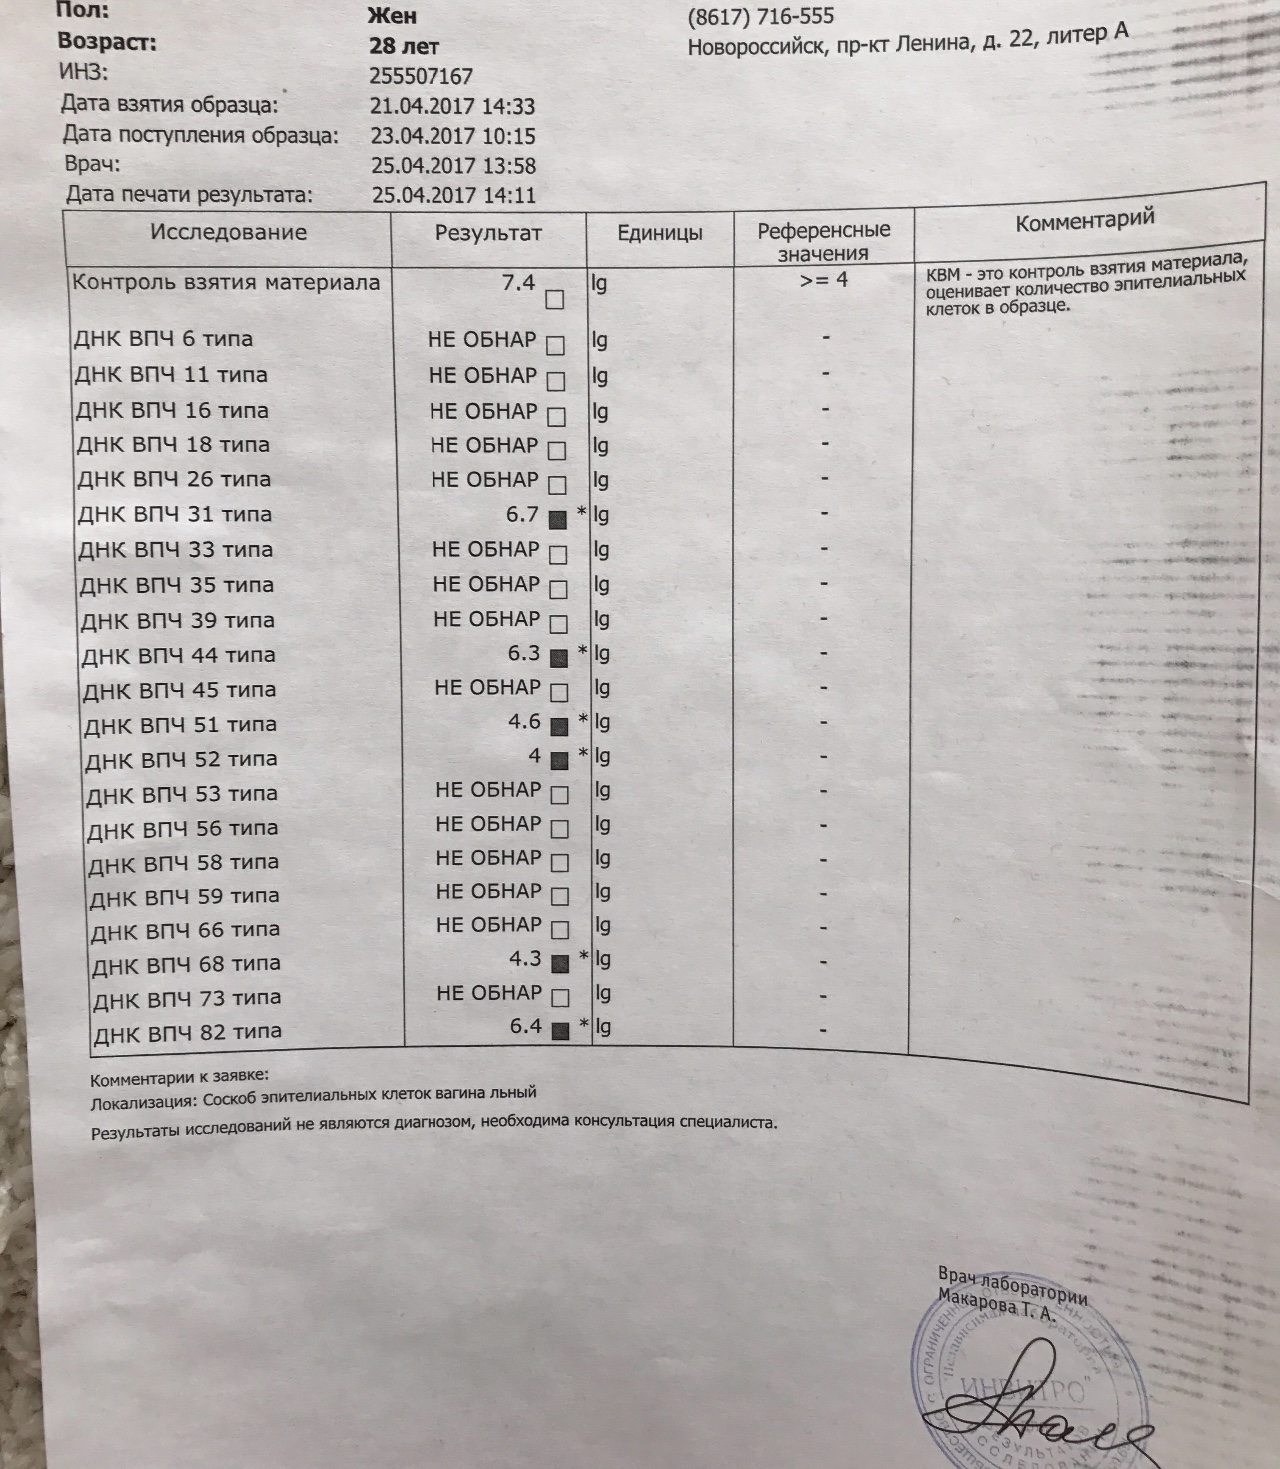

Кондиломы - это одно из самых распространенных заболеваний, передающихся половым путем. Они вызваны вирусом папилломы человека (ВПЧ) и могут появляться на внешних половых органах, анусе, ротовой полости и других областях тела.

Симптомы кондилом могут варьироваться, и визуальное представление этого заболевания может быть различным. Некоторые кондиломы выглядят как небольшие бугорки или бородавки, в то время как другие могут иметь форму плоских пятен или цветных наростов.